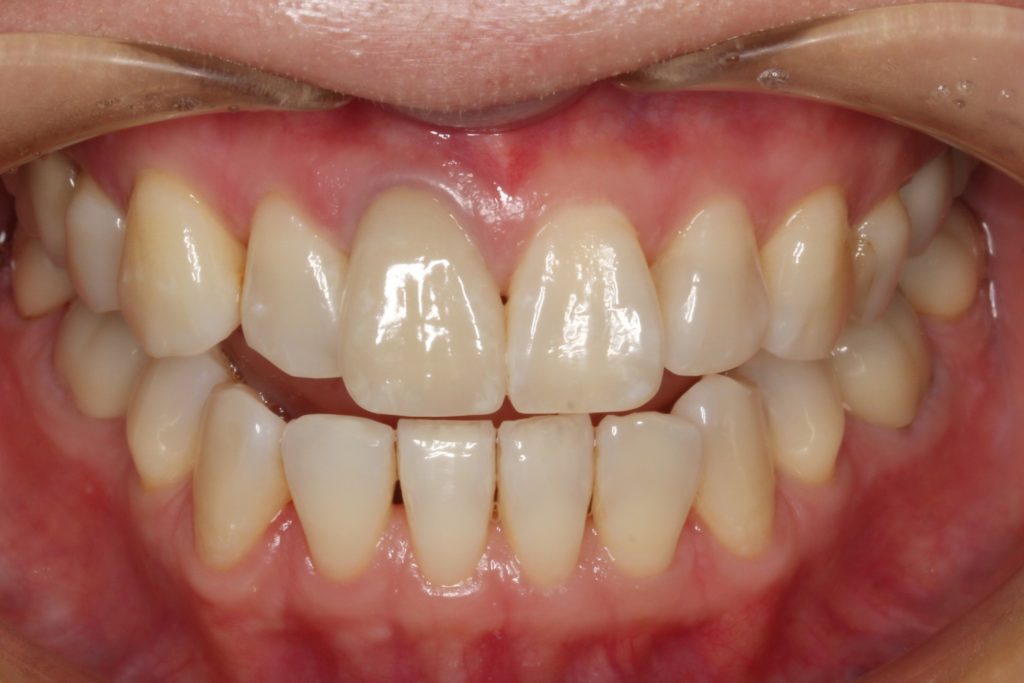

歯が装着された状態です。

パッと見るとどこを治療したか分からないくらいになっています。

綺麗に仕上がっています(^^)/

元々の歯ぐき下がりや、元の歯の暗い色を完璧に治療することは困難ですが、患者さんは満足していただけました。

治療で綺麗に審美的に改善しましたね。